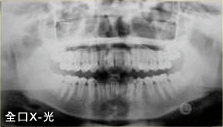

- b. 全口及側顱X光檢查。